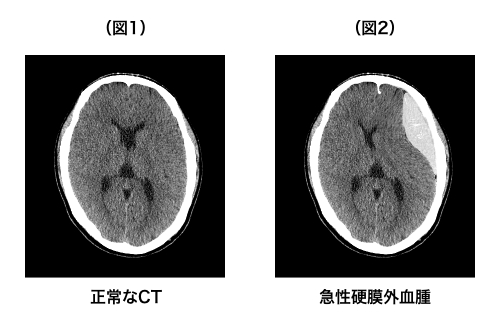

急性硬膜外血腫、急性硬膜下血腫、脳挫傷は頭部の外傷の直後に頭の中に急激に出血が起こるという点では同じですが、出血が起こる部位が異なります。硬膜という脳を包む膜の外側に出血が起これば急性硬膜外血腫(図2)、硬膜の下で脳よりも外側に起これば急性硬膜下血腫(図3)、脳そのものが傷ついて出血した場合は脳挫傷です(図4)。

※(図1)は正常なCTであり、院長自身を撮影したもの、他の出血の画像は(図1)を加工したものです。

※(図2)凸レンズ型の血腫が特徴的

※(図3)三日月型の血腫が特徴的

※(図4)脳の内部に白と黒が入り混じったような画像が特徴的